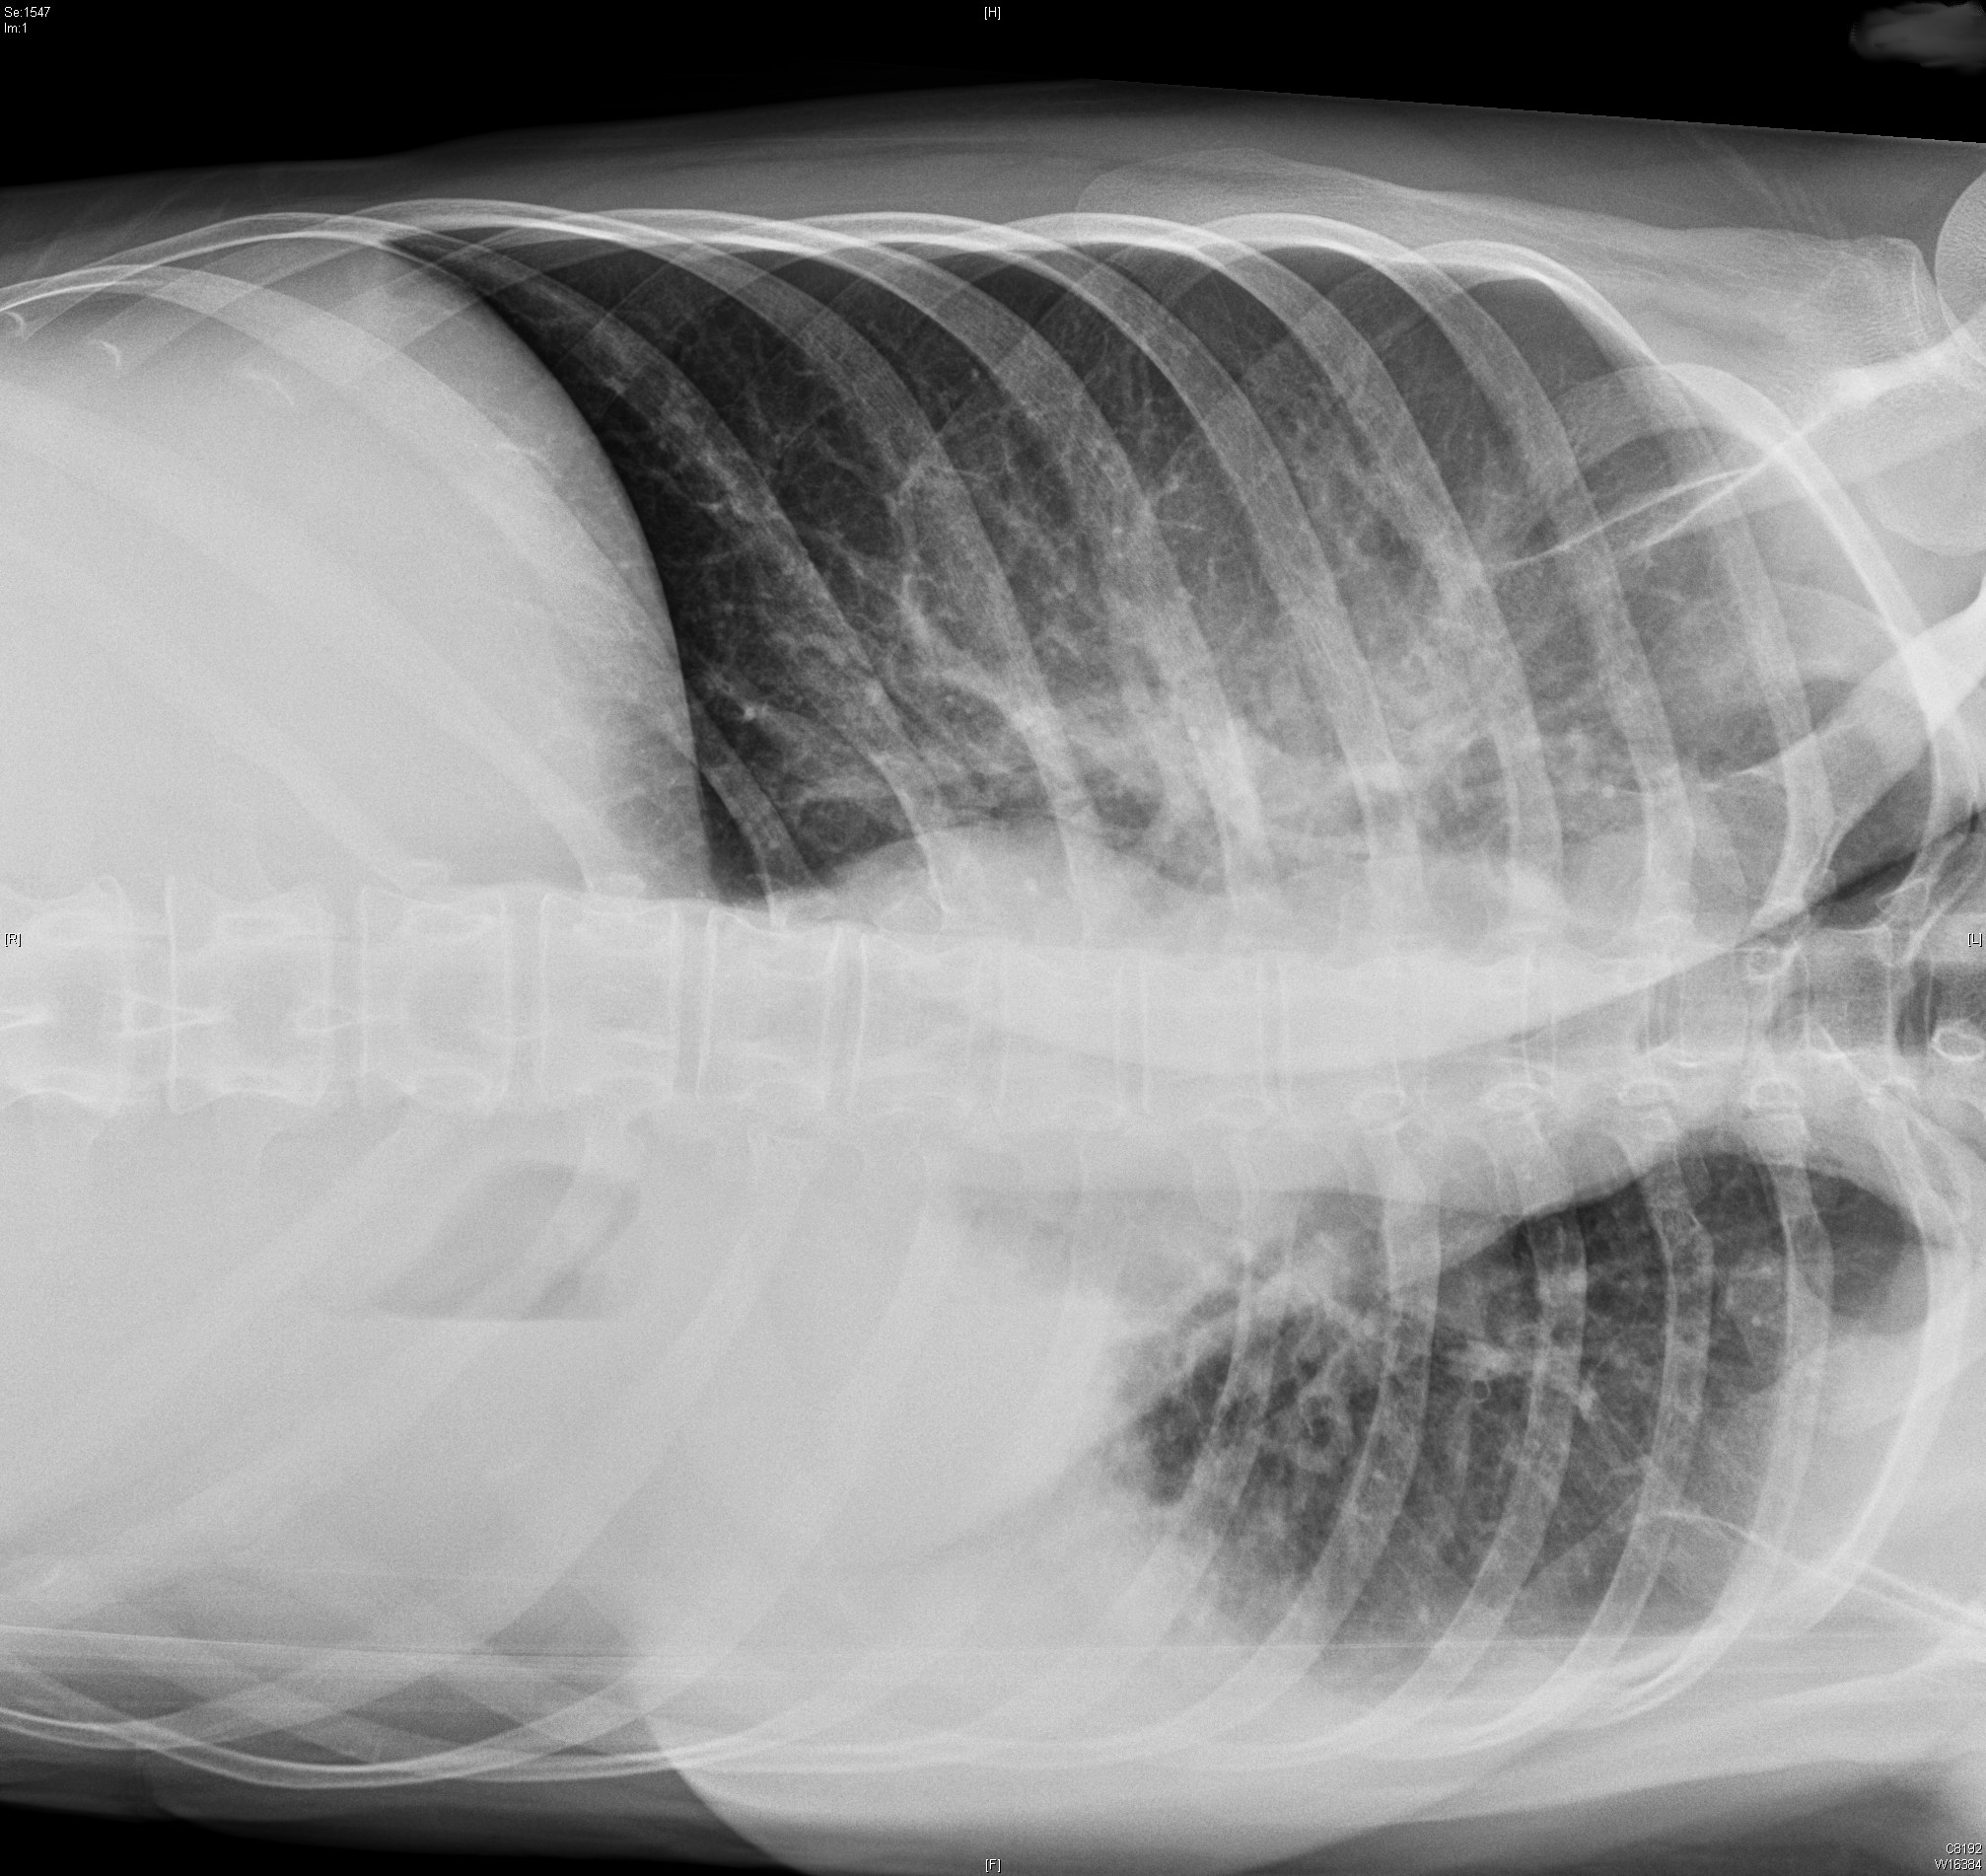

• Rx tórax AP y Perfil: que son las siguientes….

En cuanto a las Rx hay cardiomegalia, hilios ingurgitados de patrón vascular con congestión parenquimatosa pulmonar. Derrame pleural izquierdo y posterior con pinzamiento de seno costo-frenico derecho.

Se trata de un paciente varon de 73 años HTA y DLP como FRCV que acude a Urgencias por Insuficiencia Cardiaca de debut y en el ECG muestra un BCRIHH no conocido previamente. Se decide ingreso para tratamiento y estudio, se realiza un eco cardio que muestra una dialtación moderada de AI+dilatación severa e hipertrofia de VI con disfunción segmentaria. Hipocinesia severa de pared inferior, lateral y antero-apical con FE 41 %. Mitral y Aórtica muy calcificadas, esta última con apertura restringida. Cavidades derechas normales. Tras estos hallazgos se realiza un Cateterismo que muestra enfermedad de 3 vasos…… Vamos, que el paciente es presentado en sesión medico-quirurgica y termina en quirófano para sustitución de valvula aórtica por prótesis biológica y triple By-pass.

ECG: Rs a 100lpm, PR 160 mseg, eje -60, BCRIHH con alteraciones secundarias de la repolarización